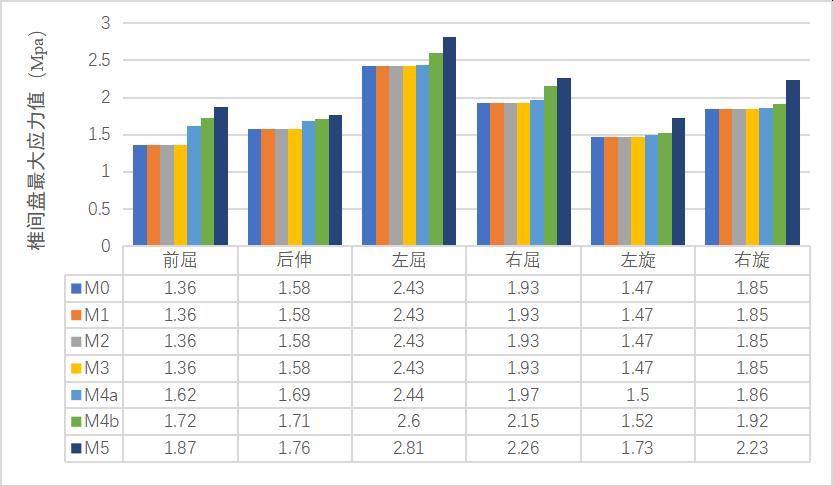

2����、0-2级成型(M1-M3)因没有进行骨质的切除��,所以对腰椎稳定性没有明显的影响����。3-4级成型时(M4a���、M4b�����、M5)����,L3-4节段在左旋及右旋时的活动度变化最大���,其中左旋由24.15%增加到30.34%����,右旋由27.81%增加到91.42%���,在前屈及左旋时的椎间盘应力值变化最明显���,其中前屈由13.64%增加到31.82%��,左旋由13.33%增加到31.33%��。L4-5节段在后伸时的活动度变化最大��,由46.49%增加到66.96%���,在前屈时的椎间盘最大应力值变化最大����,由19.12%增加到37.50%���,见表3-8��。

(2)椎间盘最大应力值变化

表格 6 成型后L3-4椎间盘最大应力值变化

表格 7 成型后L4-5椎间盘最大应力值变化

表格 8 L3-4���、L4-5节段3-4级成型后椎间盘最大应力值与正常模型比较